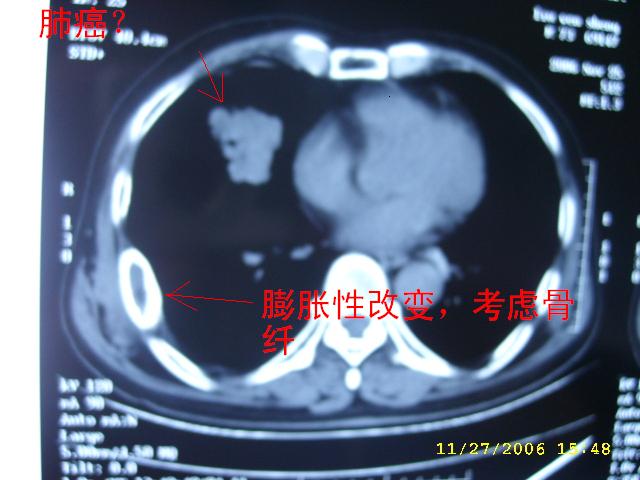

肺癌?片子少,再发!

如果右肺病变与肋骨病变联系起来考虑:1右肺周围ca并肋骨转移;2:嗜酸性肉牙肿?

肺部病变先考虑周围性肺癌,肋骨病变不象破坏和转移,应考虑骨纤.一影论影.

1右肺周围ca

2骨纤维异常增埴症

右侧周围型肺癌伴肋骨转移.

肺部的病灶是比较肯定的,但肋骨骨质完整,未见破坏征象,故肋骨考虑骨纤维异常增殖症。

1.右下肺病灶周围型肺癌的可能性非常大。

1.右侧周围型肺癌.

2.肋骨病变虑骨纤维异常增殖症.

肺部病变考虑周围性肺癌,肋骨病变考虑骨纤